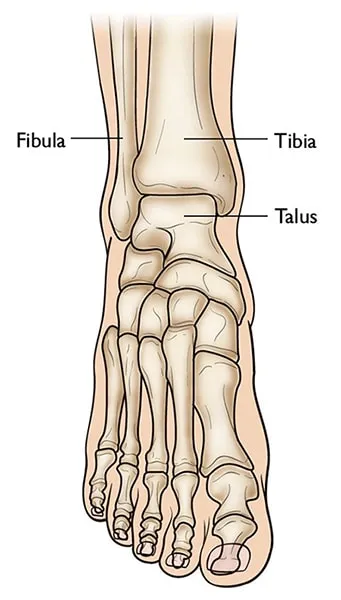

Een pilonfractuur of tibiaplafondfractuur is een ernstige breuk van het scheenbeen net boven de enkel, waarbij het gewrichtsvlak van de enkel betrokken is. Bij een pilonfractuur is het onderste deel van het scheenbeen verbrijzeld. Vaak breekt ook het kuitbeen bij dit letsel. Een pilonfractuur ontstaat meestal door hoogenergetisch trauma, zoals een val van grote hoogte (bijv. van een ladder of dak) of een zwaar verkeersongeval. De kracht van de impact duwt het sprongbeen (talus) als een stamper (pilon) in het scheenbeen, waardoor het scheenbeen bij de enkel versplintert.